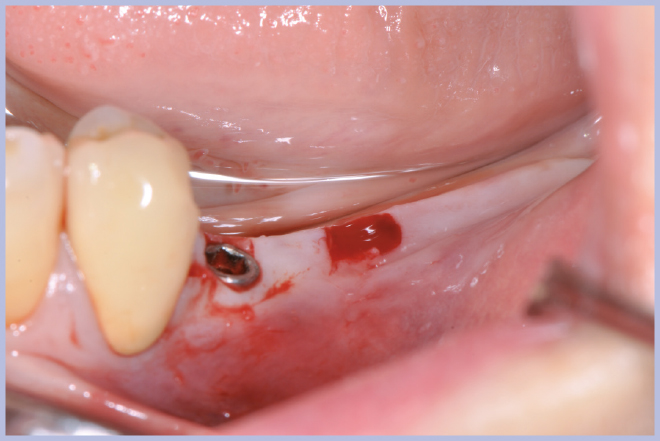

Viene quindi richiesto al tecnico di modificare in laboratorio la mascherina radiologica mediante il posizionamento delle boccole di guida adatte agli impianti da posizionare (Exacone® 6.5 e Exacone® 3,3×8) in asse con gli analoghi del modello Master 3D ed eliminando il repere radiologico standardizzato, trasformandola così nella dima chirurgica (Figg. 14, 15). Si procede quindi alla prova della mascherina sulla paziente per verificarne la stabilità e la corrispondenza esatta con il modello Master 3D (Fig. 16). La seduta chirurgica con tecnica flapless, guida chirurgica e Frese Zero1 dedicate non presenta alcuna difficoltà ; al termine dell’inserimento si posizionano sugli impianti tappi di guarigione bassi per permettere loro di guarire con tecnica sommersa (Figg. 17-27). Si effettua nella stessa seduta una CBCT che dimostra che la posizione clinica degli impianti risulta sovrapponibile a quella progettata dagli Autori (Figg. 28-30).

- Fig. 22 – Posizionamento impianto Exacone® Ø 3,3 con tappo basso

- Figg. 23-27 – Procedura guidata per inserimento impianto corto Exacone® 6.5

- Fig. 24

- Fig. 25

- Fig. 26

- Fig. 27